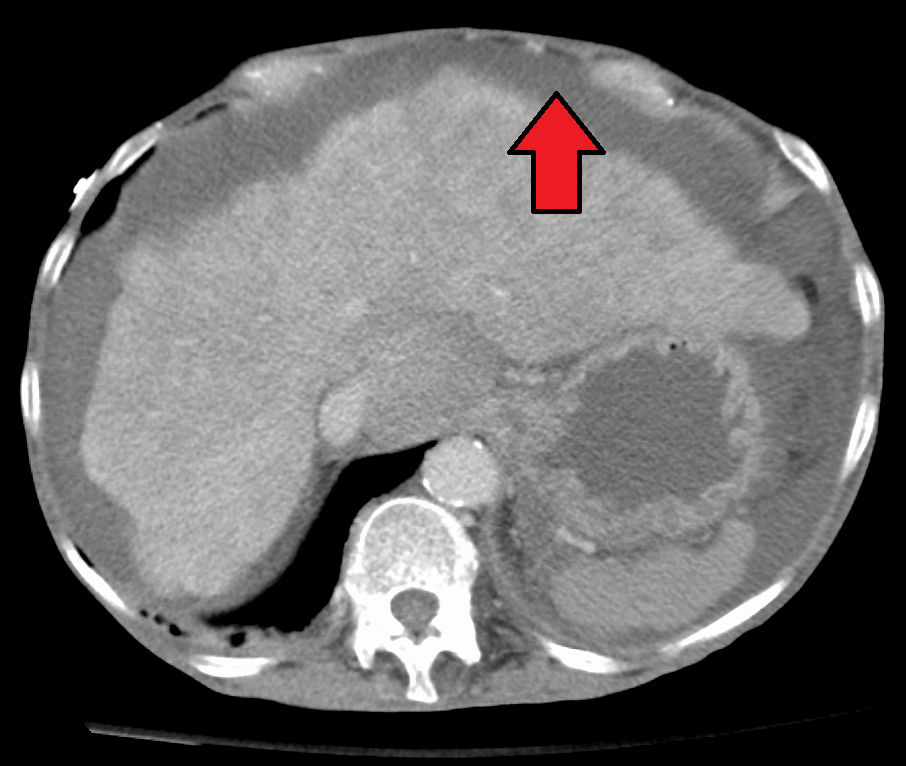

복수가 축적되면 체중 증가, 복부 팽륭, 뇨량 감소가 나타나며, 타진, 촉진상 이상 소견이 나타난다. 복부 초음파 검사나 복부 CT를 통해 진단할 수 있다.

4. 2. 영상 검사

초음파 검사는 100mL 이상의 복수가 차 있는 경우 진단 가능하며, 복부 장기의 크기와 모양을 보여줄 수 있고, 도플러 검사를 통해 문맥의 흐름 방향을 보여주거나 바드-키아리 증후군(간정맥 혈전증) 및 문맥 혈전증을 감지할 수 있다.[13] 초음파 검사자는 복수액의 양을 추정할 수 있으며, 배액이 어려운 복수는 초음파 유도하에 배액할 수 있다. 복부 CT 스캔은 복부 장기 구조와 형태를 파악하는 데 초음파보다 더 정확하다.[13]4. 3. 복수 천자

초음파 검사는 복부에서 체액을 제거하기 전에 자주 시행된다. 이는 복부 장기의 크기와 모양을 보여줄 수 있으며, 도플러 검사를 통해 문맥의 흐름 방향을 보여줄 뿐만 아니라 바드-키아리 증후군 (간정맥 혈전증) 및 문맥 혈전증을 감지할 수 있다. 초음파 검사자는 또한 복수액의 양을 추정할 수 있으며, 배액이 어려운 복수는 초음파 유도하에 배액할 수 있다. 복부 CT 스캔은 복부 장기 구조와 형태를 파악하는 데 초음파보다 더 정확하다.[13]